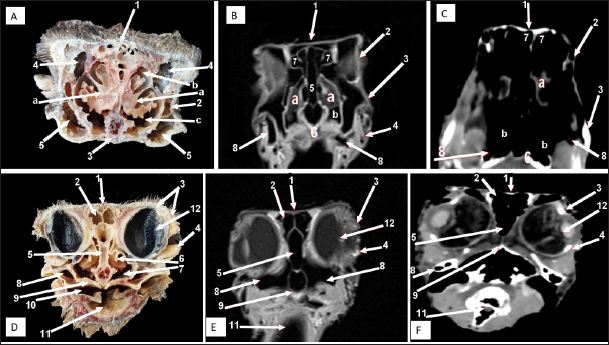

The ostrich’s cranial cavity was bounded by frontal bone dorsally, basioccipital and basisphenoid bones ventrally, supraoccipital and parietal bones caudally, interorbital septum rostrally, and temporal bone laterally. The parietal, sphenoid, and temporal bones were pneumatic (Figs. 2, 3, 9, and 10).

The brain was divided into three parts: the hindbrain (medulla oblongata and cerebellum), the midbrain (cerebrum’s peduncles and optic lobes), and the forebrain (thalamus, pineal body, hypophysis, optic tracts, and chiasm, cerebral hemispheres, and olfactory lobes) (Figs. 2, 9, and 10). The sagittal section of the brain includes the olfactory bulb, cerebrum, cerebellum, medulla oblongata, optic lobe, optic chiasm, and hypophysis (Fig. 2). The dorsal median longitudinal fissure separates the cerebrum into two hemispheres. The sagittal prominence (west) was present on both sides of this fissure (Figs. 9 and 10).

The CT pictures revealed the skull as a readily discernible white structure due to its high CT density, while the brain appeared as a grey structure due to its intermediate density. However, the settings utilized made it impossible to identify different areas of the brain in the CT scans (Figs. 9 and 10C, F). The MRI pictures showed the brain as a whitish structure with a high signal intensity. This technique was used to identify various brain structures, including the hindbrain (medulla oblongata, and cerebellum), the midbrain (peduncles of the cerebrum, optic lobes), and the forebrain (thalamus, pineal body, hypophysis, optic tracts and chiasm, cerebral hemispheres, and olfactory lobes) (Figs. 2B, 9 E, and 10E). Additionally, the olfactory bulb, cerebrum, cerebellum, medulla oblongata, optic lobe, optic chiasm, thalamus, and hypophysis.

Fig. 8. Rostral-caudal cross sections of the adult ostrich head—level 3. Rostral views of A) photograph of an anatomical cross section, B) MRI and computed tomography images showing: 1- Os nasalis, 2- Frontal sinus (divided by septea), 3- Lateral nasal process, 4-Os jugalis, 5- Vomer (pneumatic), 6- Nasal septum (two ridges separated by an empty groove), 7- Laryngeal cartilage, 8- Laryngeal cavity, 9- Eye ball, 10- Infra orbital sinus, 11- Choanae. Caudal view of D) an anatomical section, E) MRI and F) computed tomography images showing: 1- Os nasalis, 2- Frontal sinus, 3- Lateral nasal process, 4- Eye ball, 5- Os jugalis, 6- Pars verticalis ethmoidale, 7- Vomer, 8- Infra orbital sinus, 9-Latyngeal cartilage, 10- Tracheal lumen surrounded by tracheal cartilaginous rings.

Fig. 9. Rostral-caudal cross sections of the adult ostrich head—level 4. Rostral views of A) photograph of an anatomical cross section, B) MRI and C) computed tomography images showing: 1- Os frontalis, 2- Frontal sinus, 3- Processus quadratojugale, 4- Eye ball, 5- Pars verticalis ethmoidale, 6- Infra orbital sinus, 7- Vomer, 8- Tracheal lumen surrounded by tracheal cartilaginous rings, 9- Sagittal eminence (wulst) of the cerebrum. Caudal views of D) an anatomical cross section, E) MRI and F) computed tomography images showing: 1- Os frontalis, 2- Processus. quadratojugale, 3- Vomer, 4- Eye ball, 5- Infra orbital sinus, 6- Trachea, 7- Cerebral hemispheres of the brain.

Fig. 10. Rostral-caudal cross sections of the adult ostrich head—level 5. Rostral view of A) photograph of an anatomical cross section, B) MRI and C) computed tomography images showing: 1- Os parietale, 2- Os basisphenoidale, 3- Cerebral hemispheres, 4- Mid brain, 5- Trachea Plate. Caudal views of D) an anatomical section, E) MRI and F) computed tomography images showing: 1- Os parietale, 2- Os basioccipitale, 3- Cerebellum, 4- Pons, 5- Trachea, 6- Os temporalis.